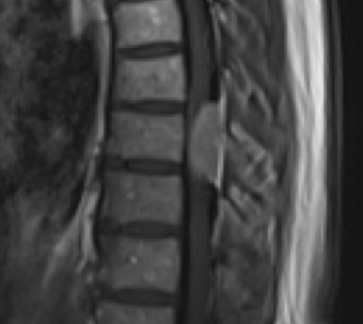

Preoperative MRI T1w demonstrating a large enhancing tumor (red arrow) causing severe cord compression and displacement (blue arrow)

Preoperative MRI T1w demonstrating a large enhancing tumor with severe cord compression